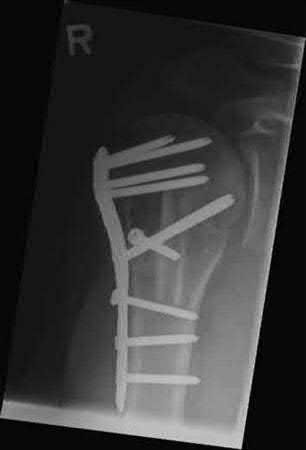

A 64-year-old woman is thrown off a horse, sustaining the injury shown in Figures A and B. She undergoes surgical fixation as seen in Figures C through E. What is the most commonly reported complication of this procedure?

The patient in the scenario has a 2-part proximal humerus fracture treated with a locking plate as seen in Figures A-E. The most common complication with the use of this implant is screw penetration. The terms screw cut out and penetration are often used interchangeably in the literature with cut out appearing more frequently in reports regarding intertrochanteric fractures.

Owsley et al retrospectively reviewed 53 proximal humerus fractures treated with locking plates and the same post-operative protocol. The most common complication was screw cut out or penetration, followed by varus displacement. They concluded that 3 and 4-part fractures in patients over 60 years have a higher incidence of failure.

Agudelo et al retrospectively reviewed 153 patients at a level-one trauma center treated with proximal humerus locking plates, investigating modes of failure for the implant. They determined that varus malreduction (head-shaft angle